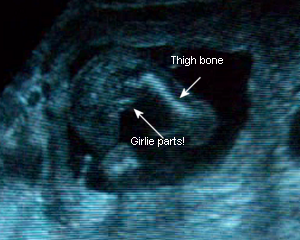

They took my weight (I’d only gained a pound in two weeks, thank God. I expected the scale to say otherwise!) and my blood pressure and sugars were fine. When they took me into the Sono room my legs were shaking and my teeth were chattering. I felt silly being that nervous, but I was! I couldn’t help it. Dr. C. came in and went over my chart. He was going to do a sono first. Yay! I asked him if he’d be checking the baby’s gender and he said yes. He’s moving the wand back and forth, taking measurements of the head, tiny thigh bones and the spine. I’m filming the entire thing. He checks the gender and says, “Ah, a little girl.” It kind of didn’t register the first time. When I hear him say it again I say, “Really?” and he says, “Yup!”

I keep staring, kind of in shock and giddy at the same time. I ask him, “Like, for real, for real?” And he says, “Yup, see, there’s her vagina!” I couldn’t contain my happiness and said, “Oh, I’m so happy!” and he said, “Que bueno.”